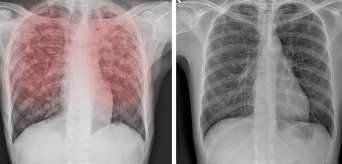

폐 결절은 건강검진 시 흉부 X-ray 검사나 저선량 흉부 CT 검사를 통해 우연히 발견되는 경우가 많습니다.

결절 크기, 모양, 위치, 석회화 여부 등을 종합적으로 고려하여 악성 여부를 판단합니다.